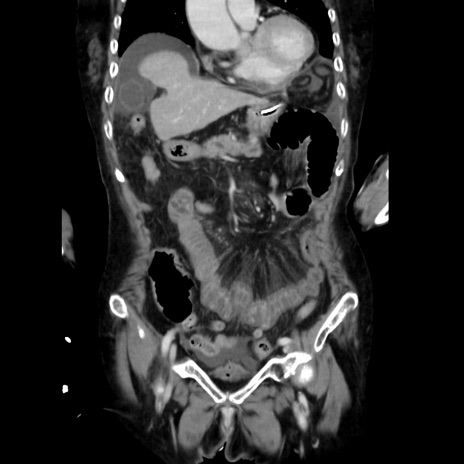

症例40(冠状断像)

【症例】90歳代女性

【主訴】腹痛・嘔吐

【現病歴】 食欲低下、嘔吐があり昨日他院受診。肺炎と診断され入院となる。入院後より腹部全体に圧痛あり。胃管留置され経過みていたが、症状持続するため、

当院転院となる。

【既往歴】胸椎圧迫骨折、胆石症

【身体所見】腹部:中央に激痛あり、圧痛あり、反跳痛不明

【データ】WBC 17100、CRP 18.82

冠状断像